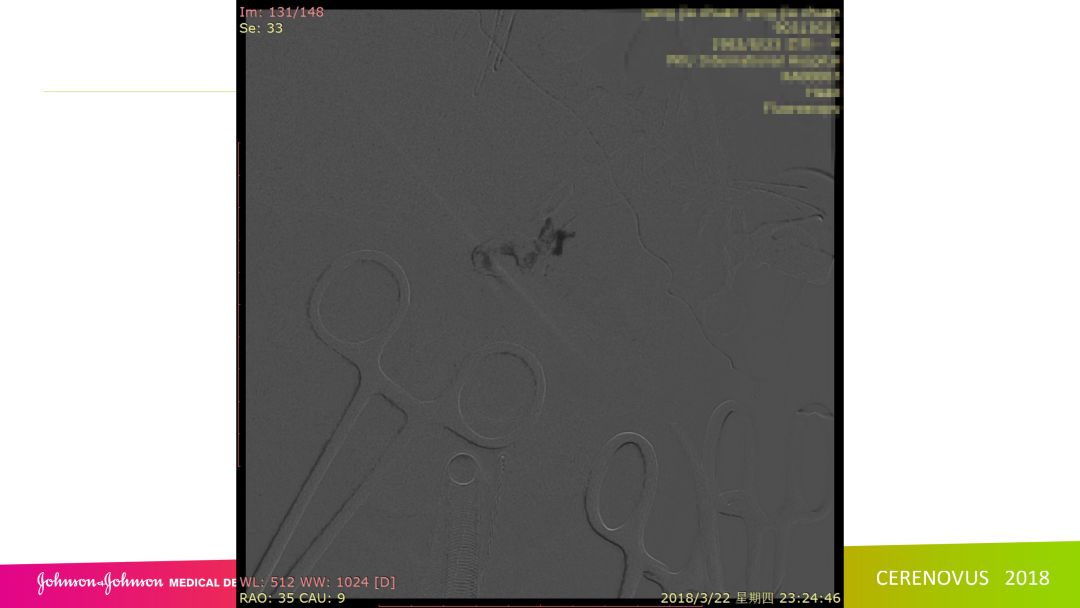

复合手术治疗海绵窦区硬脑膜动静脉瘘一例